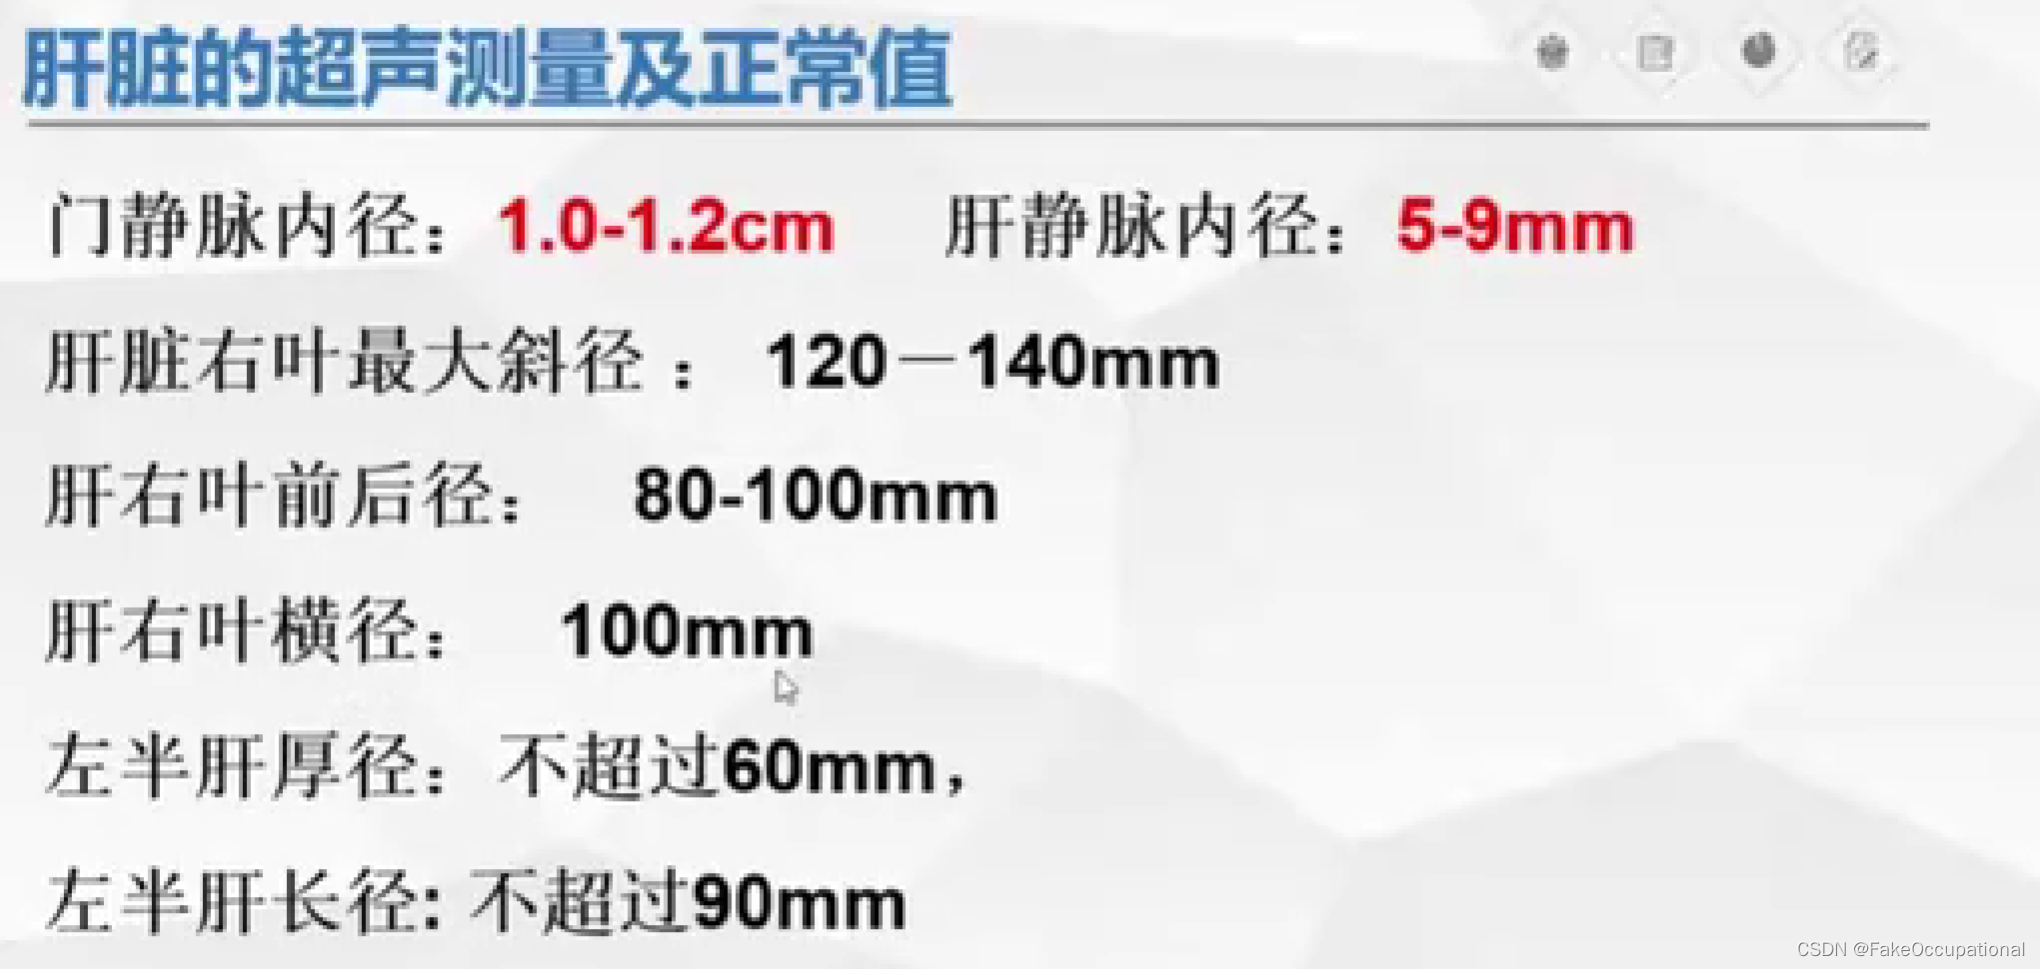

肝脏解剖概要

肝脏超声检查技术

正常肝脏超声表现